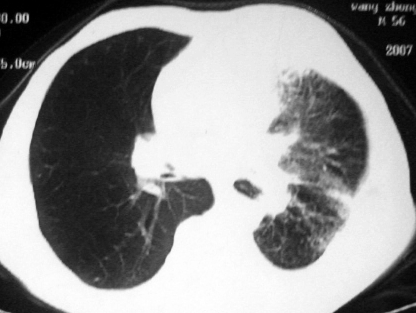

男,54岁,咳嗽,气喘半年,胸痛一月.

血性胸水

左侧胸腔积液 斜裂积液 心包积液 左肺不张 考虑左肺ca并胸膜心包转移。

支持左肺下叶中心型肺癌(累及舌叶)伴阻塞性肺炎、膨胀不全、胸腔积液、心包少量积液。

考虑左肺下叶中央型肺癌伴阻塞性肺炎及肺不张,纵隔受累可能,胸膜转移。